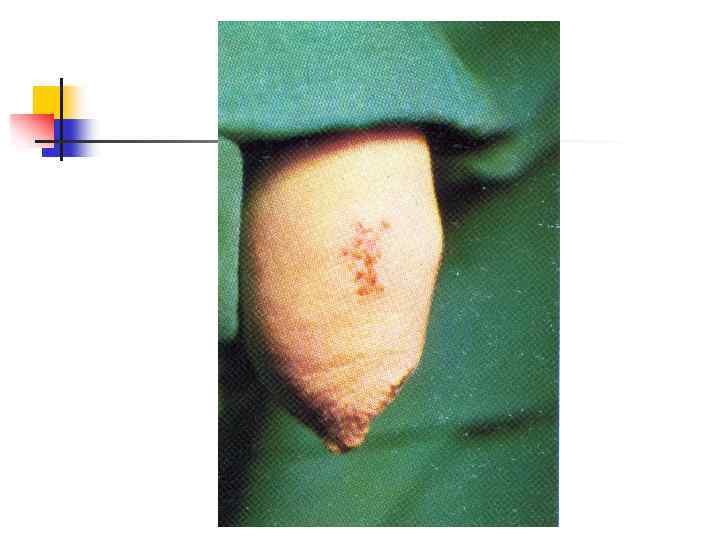

Герпес половых органов: рецидив На теле полового члена группа везикул, сидящих на гиперемированном, слегка возвышающемся основании. В центре некоторых везикул образовались корки

Герпес половых органов: рецидив На теле полового члена группа везикул, сидящих на гиперемированном, слегка возвышающемся основании. В центре некоторых везикул образовались корки